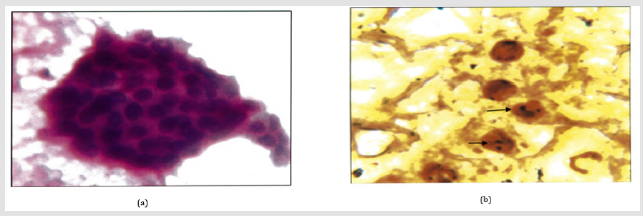

Figure 4: a: Lymphocytic throditis .(H&E.400X) Lymphocytic infilterate.

b: Intra Nuclear brown/black dots are seen in a case of in a of lymphocytic thyroiditis. AgNOR Score=1.69(1000X).